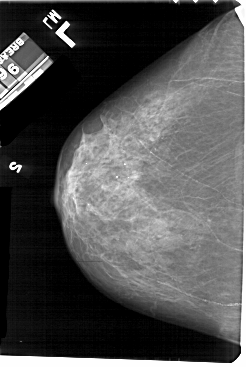

A_1697_1.RIGHT_CC

LEFT_CC LINES 5491 PIXELS_PER_LINE 3676 BITS_PER_PIXEL 12 RESOLUTION 43.5 NON_OVERLAY